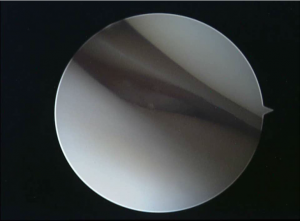

The diagnosis of hypermobile lateral meniscus is a clinical diagnosis only confirmed during the arthroscopy.

A newly described test can help : Tom´s test